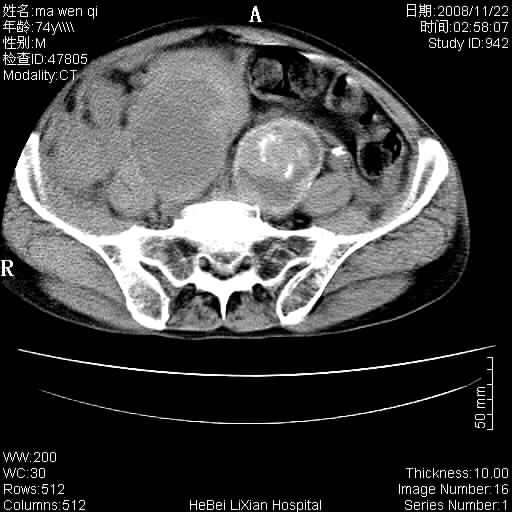

患者男 74岁.突然昏迷,休克6小时.血压70/30,头颅ct未见异常,既往体健.

补充病史,保留导尿10小时,尿袋内只有少许尿液,患者于住院后15小时后去世.

腹主动脉、双侧髂动脉夹层动脉瘤破裂出血进入腹腔。

考虑双侧髂a瘤,伴破裂出血

1)考虑双侧髂动脉瘤并右侧动脉瘤破裂出血,右侧腹膜后及腹腔积血。2)双侧腹股沟疝。

1)考虑,腹主动脉、双侧髂动脉夹层动脉瘤破裂伴右侧腹膜后及腹腔积血。2)双侧腹股沟疝。

1)考虑胸、腹主动脉、双侧髂动脉瘤并右侧动脉瘤破裂出血,右侧腹膜后及腹腔积血。2)双侧腹股沟疝。